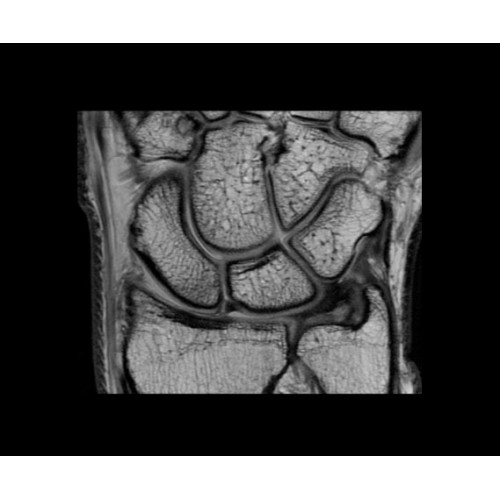

SIGNA PET/MR 3.0T — это гибридная система, в которой совмещаются две принципиально разные технологии — магнитно-резонансную томографию (МРТ) и позитронно-эмиссионную томографию (ПЭТ). Система отличающийся высокой чувствительностью и эффективностью и предназначена для диагностики в области онкологии, неврологии, кардио-васкулярных исследований, исследований воспалительных процессов.

Компания GE Healthcare представляет революционную, полностью интегрированную систему SIGNA PET/MR1, в которой сочетаются времяпролетная технология (TOF) и возможности напряженности магнитного поля 3.0 Тл. Мы поможем вам поднять исследования на более высокий уровень. SIGNA PET/MR позволяет достичь впечатляющей точности и скорости исследований, а благодаря новейшей технологии реконструкции Q.Clear2 качество изображений улучшается в два раза. Кроме того, в систему включен полный набор клинических приложений и гибких катушек для проведения любых видов исследования, открывая для вас возможности визуализации, о которых вы даже не догадывались.

В систему SIGNA PET/MR встроены запатентованные детекторы кремниевого фотоумножителя (SiPM) и сверхчувствительные кристаллические сцинтилляторы на основе лютеция толщиной 25 мм. Благодаря этому обеспечивается исключительная чувствительность и возможность использования времяпролетной диагностики (TOF).

Кроме того, в результате использования технологии TOF и инновационной технологии реконструкции Q.Clear вы сможете добиться прекрасного соотношения сигнал/шум. А благодаря технологии нулевого времени эхо (ZTE) визуализировать костную структуру без ионизирующего излучения. Все эти разработки для улучшения качества сканирования и точности анализа помогут вам использовать весь потенциал ПЭТ/МРТ.

• МРТ с функцией нулевого времени эхо (ZTE) отличается точностью, возможностью персональных настроек и отсутствием ионизирующего излучения. Она приходит на смену традиционному исследованию на основе рентгеновского излучения. МРТ с функцией нулевого времени эхо (ZTE) на базе SIGNA ПЭТ/МРТ является более надежной и быстрой по сравнению с системами, использующими сверхмалое время эхо (UTE).